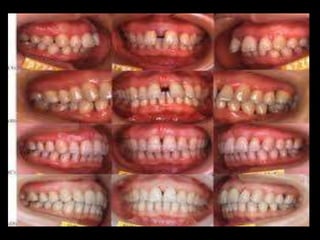

9 mm probing depth 8 mm probing depth 2 mm probing depth

3mm probing depth 11mm probing depth 2mm probing depth

Clinically, localized juvenile periodontitis (LJP)

patients rarely show calculus or plaque formation

and often exhibit little or no gingivitis.

However, deep probing, attachment loss,

radiographic bone loss are found. Deep

interproximal vertical bone loss on first molars

and incisors are characteristic of LJP. Juvenile

periodontits should be identified and treated

early with antimicrobial therapy, scaling and

root planing, and also surgery according to

extent of destruction.